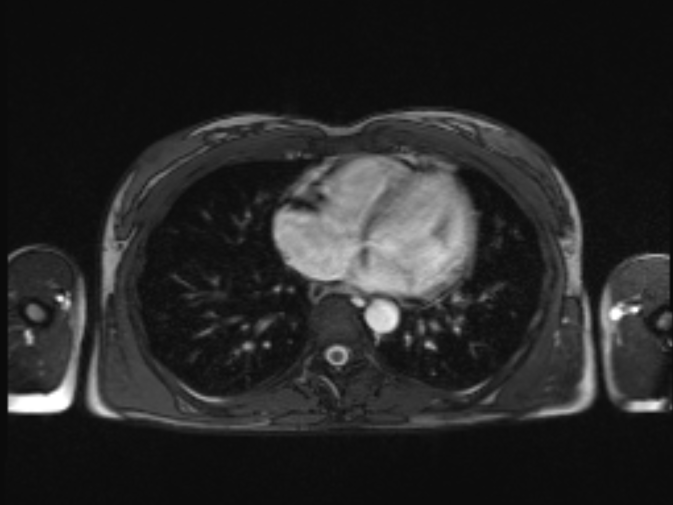

Kurzer Ausflug ins MRT: Aorta-Schnappschüsse und Gewürm

Ständig predige ich Wein und trinke Wasser. Oder andersrum? Jedenfalls war ich heute, nachdem ein Angiologe mir bereits vor drei Jahren zur Abklärung einer Auffälligkeit an meiner Aorta ein MRT empfohlen hatte, endlich in der Radiologie und ließ mich durchleuchten. Noch habe ich keinen Bericht, aber wenn es euch interessiert, könnt ihr trotzdem ruhig mal einen Blick auf mein Inneres werfen.… Weiterlesen